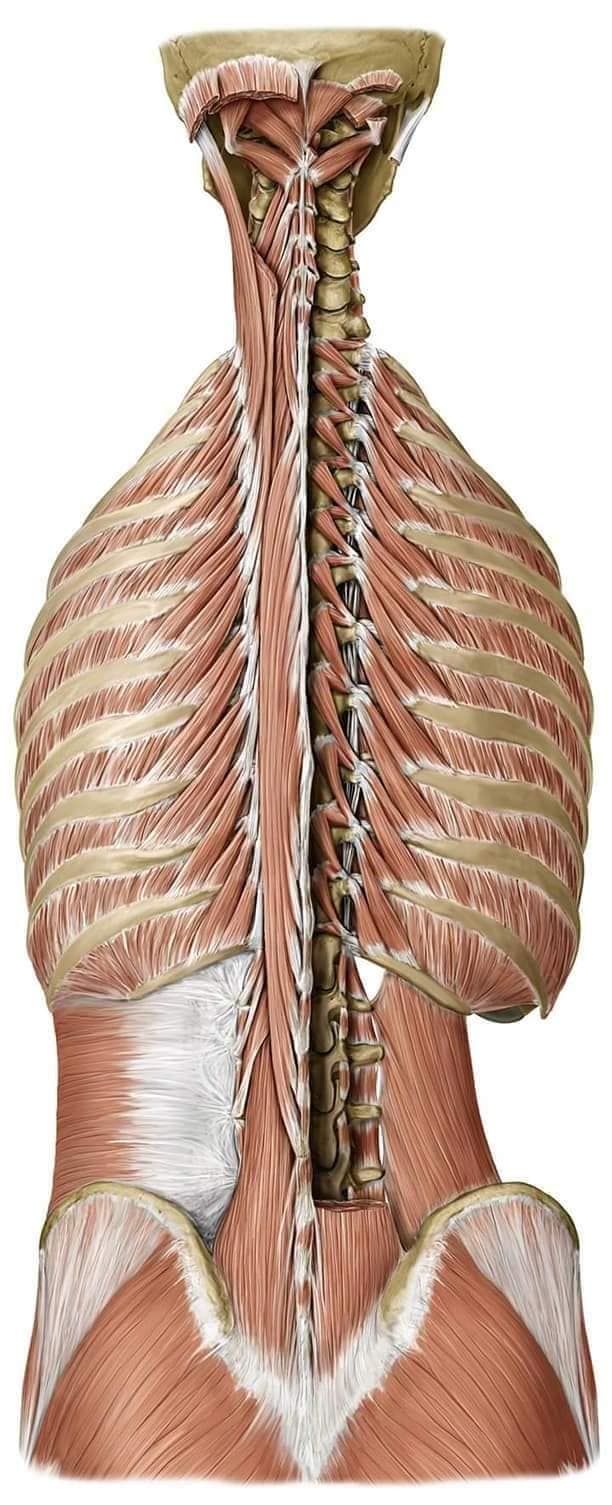

Спинні м'язи

Спинні м'язи виконують функції підтримки хребта, а також дозволяють здійснювати рухи тулуба.

Глибинні спинні м'язи

М'язи, що забезпечують стабільність хребта: М'язи, що розташовані між хребцями: включають мускулатуру, яка забезпечує стабільність і підтримку хребта, а також дозволяє здійснювати рухи хребта.

М'язи, що здійснюють ротацію та нахили

М'язи, що забезпечують ротацію хребта: Ротаційні м'язи: допомагають у здійсненні обертальних рухів тулуба, а також у підтримці рівноваги і стабільності хребта.